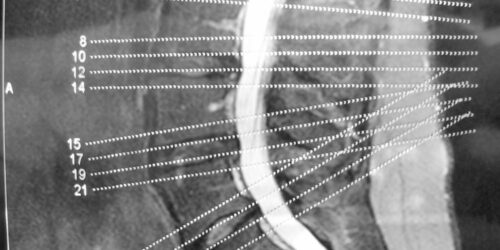

A brief overview of degenerative disc and joint disease

When you mention the term degenerative disease, it refers to the gradual deterioration of the body tissues or cells over the years due to the natural aging process.  As we age, our spine starts giving in to the stress of providing flexibility and support to our back. The components of the spine start deteriorating slowly, and you will experience back pain and stiffness in the spine.